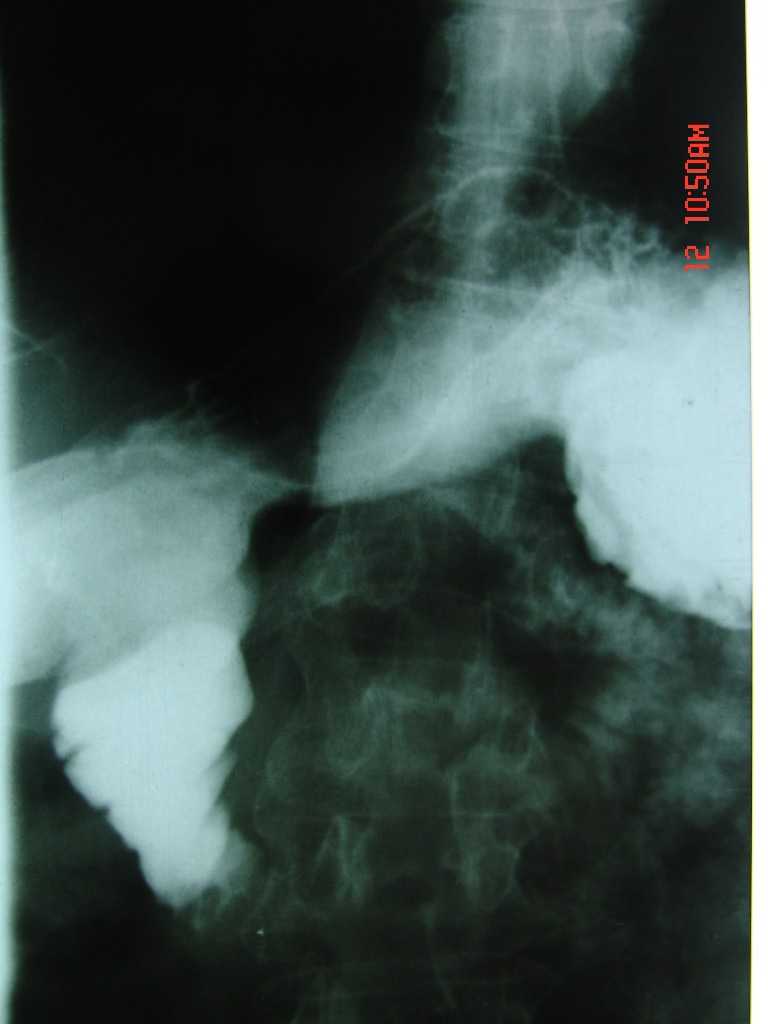

胃体部粘膜不规则增厚,胃肠造影也显示充盈缺损-胃溃疡?胃癌?

十二指肠降段扩张,水平段狭窄成鼠尾状,肠壁明显增厚,胰腺勾突增大成不均匀强化,其内可见低密度区,胆囊增大,1十二指肠水平段腺癌侵犯胰腺勾突可能大,2胰腺癌侵犯十二指肠(只有胆囊增大没有肝内外胆管扩张不好解释)代除外.

上消化道造影见十二指肠结节状充盈缺损,ct增强十二指肠壁局限性增厚并强化,考虑十二指肠壶腹癌?

十二指肠降段扩张,水平段狭窄成鼠尾状,肠壁明显增厚,胰腺勾突增大成不均匀强化,其内可见低密度区,胆囊增大,1十二指肠水平段腺癌侵犯胰腺勾突可能大,2胰腺癌侵犯十二指肠 。

今日手术结果:胰腺钩突癌侵犯十二直肠,腹腔淋巴结转移.